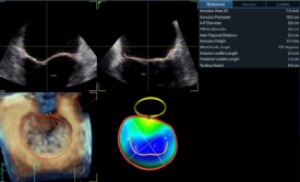

TAVI

- Paravalvular Leak After Transcatheter Aortic Valve Replacement. The New Achilles’ Heel? A Comprehensive Review of the Literature - https://www.ncbi.nlm.nih.gov/pubmed/23375925

- Aortic regurgitation after transcatheter aortic valve implantation: mechanisms and implications. http://cdt.amegroups.com/article/view/1552/2256

- La soluzione Valve ASSIST 2 comprende TAVI Analysis, HeartVision 2 e richiede una workstation AW con Volume Viewer, Volume Viewer Innova. Queste applicazioni sono vendute separatamente.